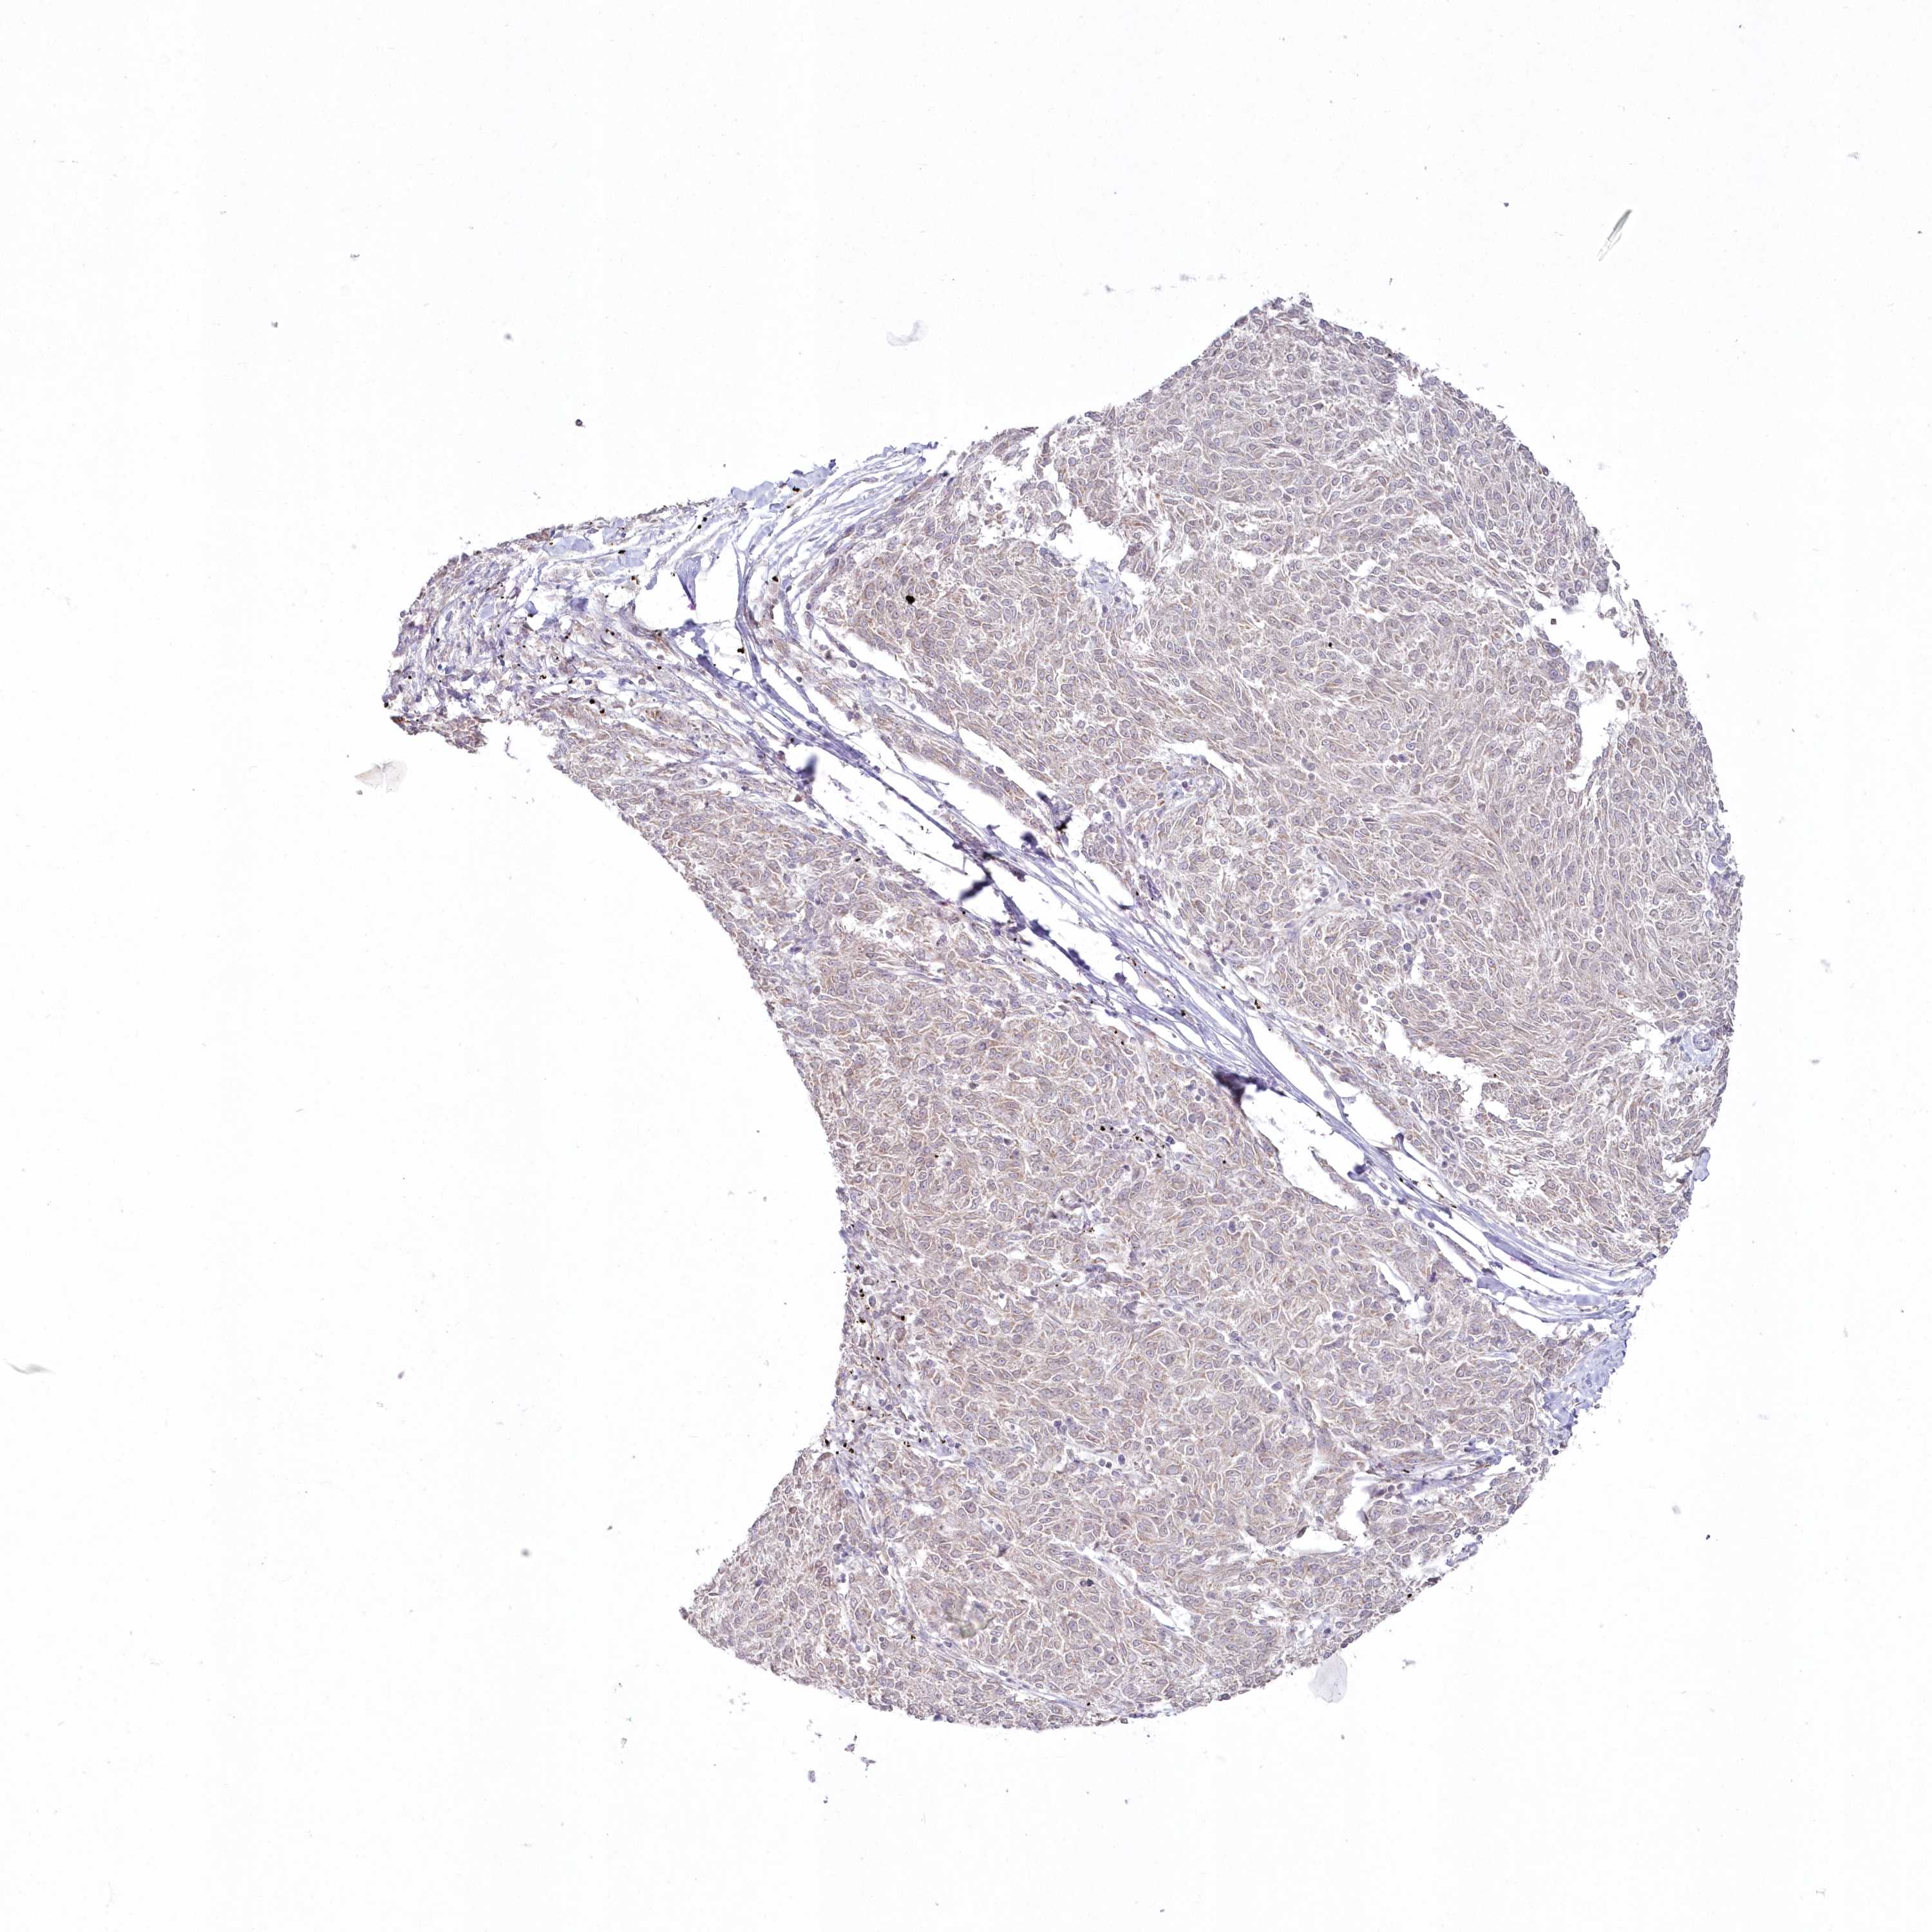

MELANOMA - Protein expressioni

A mouse-over function shows sample information and annotation data. Click on an image to view it in a full screen mode. Samples can be filtered based on level of antibody staining by selecting one or several of the following categories: high, medium, low and not detected. The assay and annotation is described here.

Note that samples used for immunohistochemistry by the Human Protein Atlas do not correspond to samples in the TCGA dataset.

Antibody stainingi

Antibody staining in the annotated cell types in the current human tissue is reported as not detected, low, medium, or high, based on conventional immunohistochemistry profiling in selected tissues. This score is based on the combination of the staining intensity and fraction of stained cells.

Each image is clickable and will lead to virtual microscopy that enables deeper exploration of all samples and also displays staining intensity scores, fraction scores and subcellular localization as well as patient and tissue information for each sample.

Antibody HPA037770

Antibody HPA037771

Staining

High

Medium

Low

Not detected

Intensity

Strong

Moderate

Weak

Negative

Quantity

>75%

75%-25%

<25%

None

Location

Nuclear

Cytoplasmic/membranous

Cytoplasmic/membranous,nuclear

Malignant melanoma, NOS

Malignant melanoma, Metastatic site